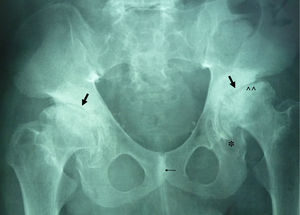

La ML III se manifiesta aproximadamente entre los 3 y 5 años de edad, con anomalías esqueléticas, alteraciones faciales, talla baja, inteligencia normal o retraso mental leve, opacidad corneal y escoliosis, a diferencia de otras formas de ML que sí tienen afectación visceral y un pronóstico vital sombrío en la infancia2,3. En la ML III la evolución es lenta, pudiendo alcanzar hasta la quinta década de la vida4. Las alteraciones óseas en la infancia pueden confundirse con artritis idiopática juvenil o esclerodermia, fundamentalmente por la afectación de las manos5,6. Los hallazgos radiológicos característicos de las manos son huesos del carpo pequeños e irregulares y falanges proximales relativamente anchas5 (fig. 1). En la columna lumbar, displasia vertebral con delineación irregular de los cuerpos vertebrales3, imágenes que se confirman en la RM (fig. 2). En la pelvis, displasia progresiva de las caderas, con acetábulos aplanados y destrucción de las cabezas femorales con coxartrosis secundaria2 (fig. 3).